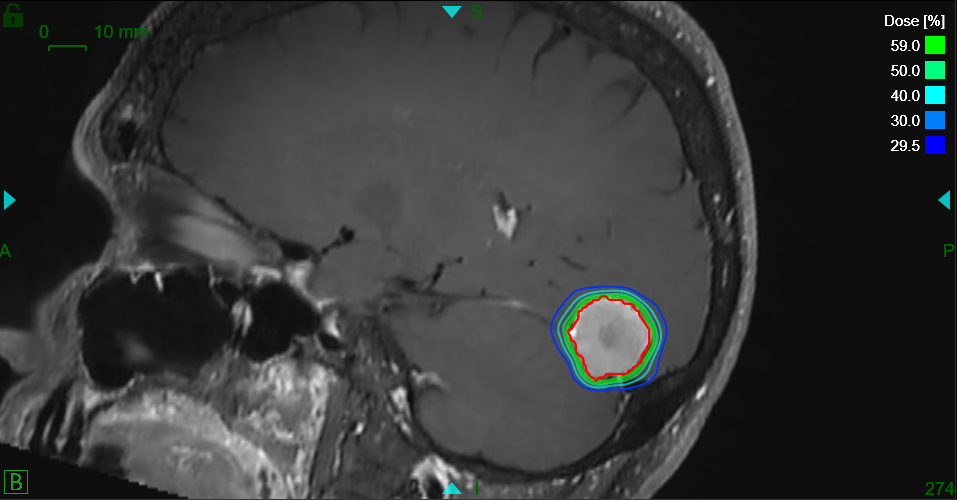

Schnell kommt die Frage nach möglichen Behandlungsformen auf. Eine Option ist die hochpräzise Radiochirurgie, welche die SNRC AG in Zürich auf dem neusten Stand der Technik mit dem ZAP-X® anbietet. Diese Form bietet den Betroffenen eine Alternative bzw. Ergänzung zur klassischen Operation oder der herkömmlichen, meist langwierigen Strahlentherapie.

Mit dem ZAP-X können Tumore, Metastasen und auch Krankheitsbilder wie Trigeminusneuralgie hochpräzise, effektiv, nachhaltig und bei gleichzeitiger Schonung des umliegenden, gesunden Gewebes therapiert werden. Die Behandlung erfolgt ambulant und ohne Narkose. Sie dauert ca. eine Stunde, ist absolut schmerzfrei und die Patienten können im Anschluss direkt nach Hause.